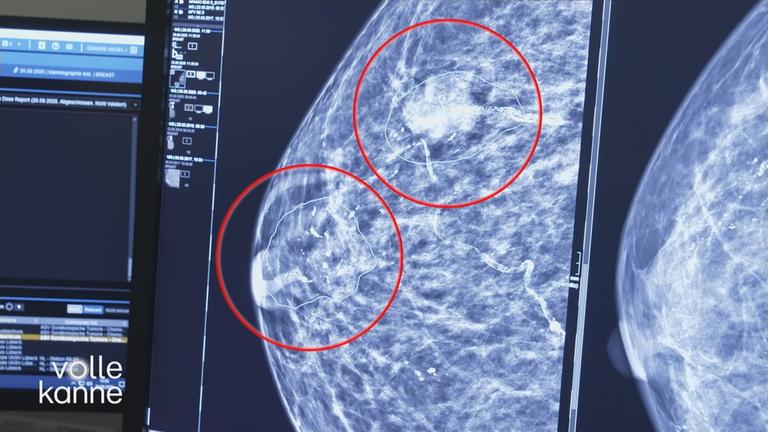

Matthias Koeberlin und Anna Werner Friedmann zu Gast. Zudem: Primärarztsystem; Matcha aus DE; KI und Brustkrebs; Streaming-Tipps; Siebengebirge; Eisen; Landminen in Angola; Kirchner und Picasso.